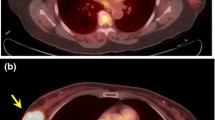

The mean ± standard deviation age of the 306 patients was 58.9 ± 13.5 years (range 30–95 years). The mean ± standard deviation size of the invasive tumours was 2.65 ± 1.83 cm (range 1.0–15.0 cm). The histological classifications of the cancers were: invasive ductal carcinoma (282 patients, 91.6 %), invasive lobular carcinoma (13 patients, 4.2 %), and other specified cancers (13 patients, 4.2 %; ten mucinous carcinomas, two apocrine carcinomas and one medullary carcinoma). The subtypes of the 308 tumours were luminal A in 87 patients (28.2 %), luminal B (HER2-negative) in 111 patients (36.0 %), luminal B (HER2-positive) in 31 patients (10.1 %), HER2-positive in 26 patients (8.4 %), and triple-negative in 53 patients (17.2 %). The clinicopathological findings and results of univariate regression analysis for the 308 breast cancers are summarized in Table 1. PET/CT imaging in representative patients is shown in Figs. 1 and 2.